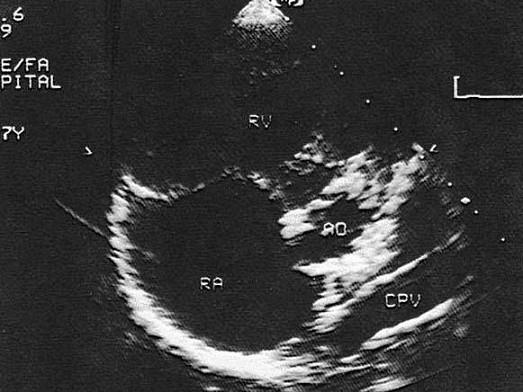

该病例最可能的诊断?(?)A.三房心B.部分性肺静脉畸形引流C.完全性肺静脉畸形引流D.瓣上环E.部分型心内膜垫缺损

问题 该病例最可能的诊断?(?)

选项 A.三房心 B.部分性肺静脉畸形引流 C.完全性肺静脉畸形引流 D.瓣上环 E.部分型心内膜垫缺损

答案 C